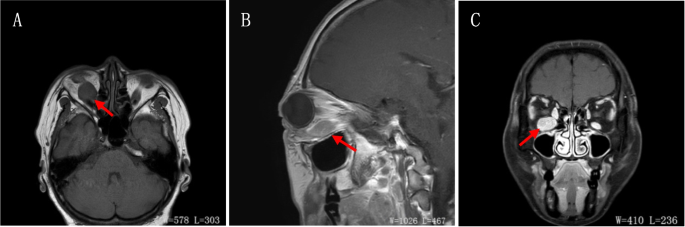

A 55-year-old female presented with swelling of the lower lid of the right eye for 2 months without redness, ocular pain, or decreased visual acuity. This patient had a long and complicated course for 6 years, as shown in Table 1. Ophthalmic examination indicated a visual acuity of 20/20 in the right eye and 20/25 in the left eye and intraocular pressure of 12 mmHg bilaterally. The right eye showed proptosis, lower lid swelling, mild conjunctival injection, and limited ocular motility when looking upward. Other aspects of the examination, including the anterior segment, optic disc, and fundus, were within normal limits in both eyes. There was no palpable regional lymphadenopathy. Magnetic resonance imaging showed significant enlargement of the right inferior rectus muscle belly (Fig. 1). Laboratory tests showed normal complete blood count, hyperuricemia, hyperlipidemia, elevated serum complement factor 4 (49.5 mg/dl), and elevated C-reactive protein (6.2 mg/L). Thyroid function tests were normal, including serum total T3, total T4, free T3, free T4, thyroid-stimulating hormone, thyroid stimulating hormone-receptor antibodies, thyroglobulin antibody, and thyroid microsomal antibody.

The clinical and radiological features of this patient lack specificity. Five visits over 6 years showed prominent enlargement of the right inferior rectus muscle belly, which is similar to the presentation of thyroid-associated ophthalmopathy (TAO). However, by carefully analyzing the patient’s imaging and exam results, there were differences between the patient’s condition and TAO. First, the typical radiological finding of TAO is a fusiform enlargement of the muscle belly, whereas this patient’s muscle had an oval change. Second, in TAO, if the right inferior rectus muscle develops to such a severe level, the rest of the extraocular muscles are also likely to be heavily involved, which was not observed in this patient. Third, the thyroid function was normal in any of all five of the visits. Fourth, the biopsy found a friable mass with a grayish fish-like cut surface, which is more consistent with the gross characteristics of malignant tumors. Even in patients with a confirmed diagnosis of TAO, continued deterioration should raise a suspicion of malignancy. Zoran et al. reported a patient with unilateral, low-grade marginal zone B-cell lymphoma simulating unilaterally worsening TAO. His previous symptoms worsened with progressive unilateral exophthalmos resistant to the previously applied glucocorticoid therapy [21].